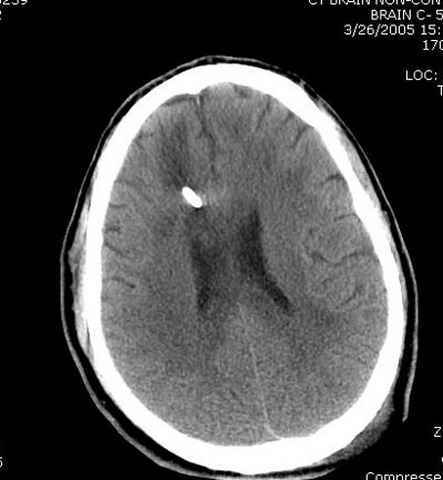

больному 42, автоавария, политравма, открытая черепномозговая травма, безсознании, открытый перелом бедра, размозжение мягких тканей, дефект кожи на передней поверхности бедра около 13 см2 от ожога, компартмент синдром.

Наблюдается службой травмы и нейрохирургии (ICP) Increased Intracranial Pressure by ventricular cateter

монииторинг